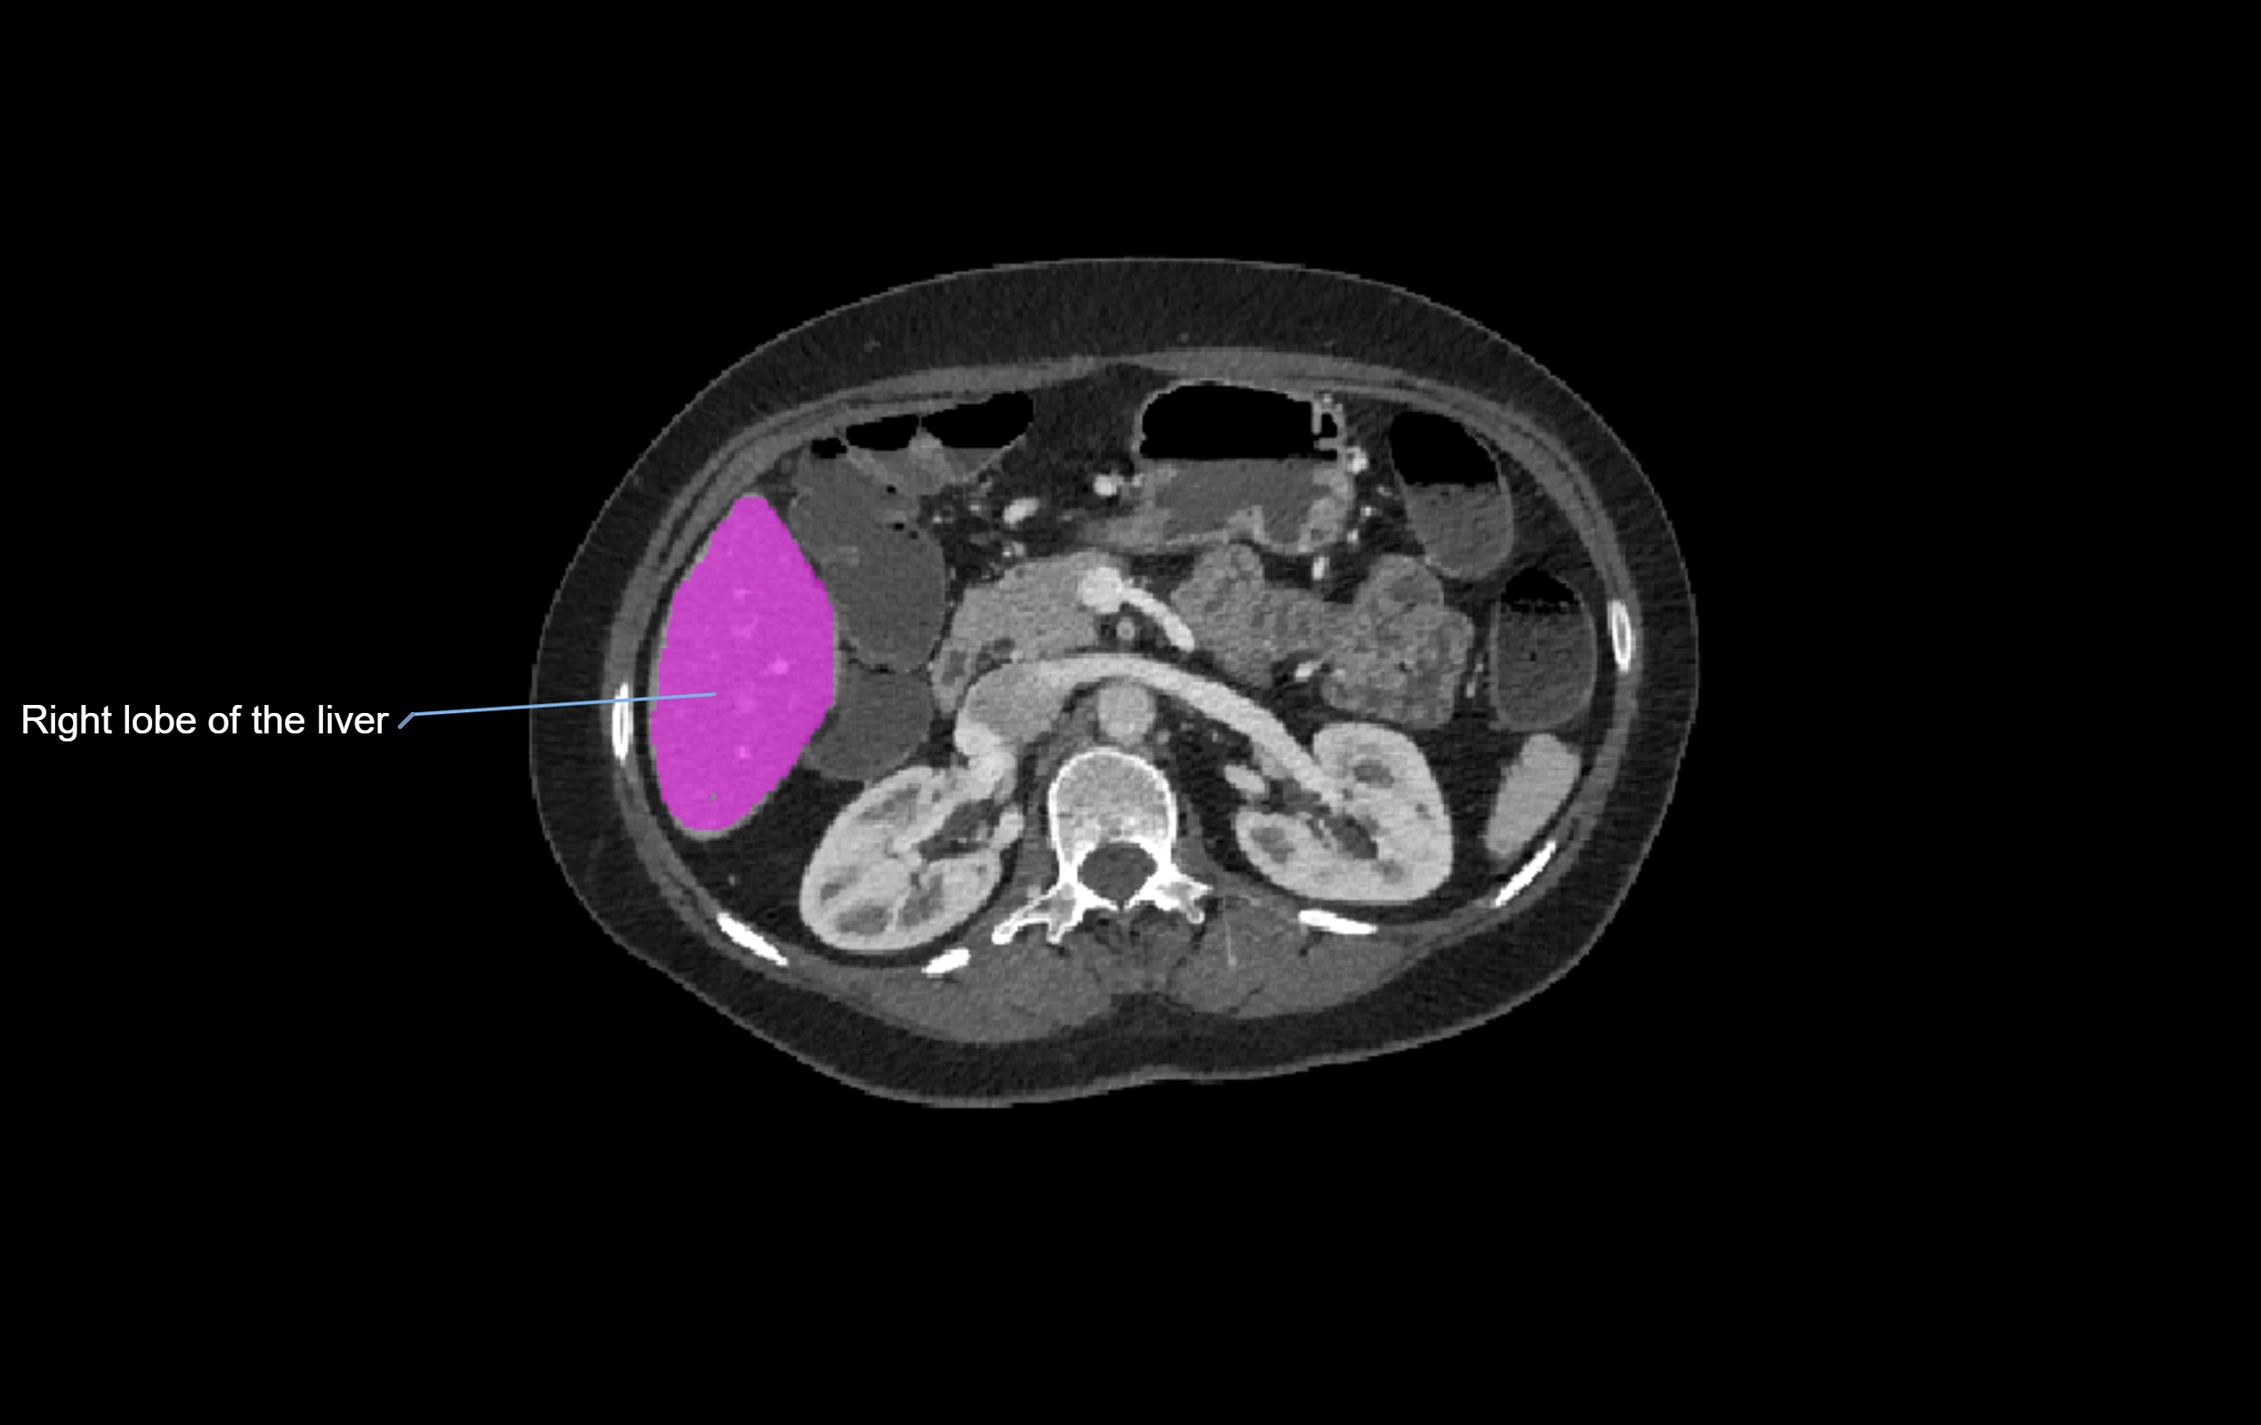

CT Pre-Contrast:

• Caudate lobe appears as a soft-tissue density, isodense to the rest of the liver

• Enlargement may be appreciated in cirrhosis or Budd–Chiari syndrome

CT Post-Contrast:

• Homogeneous enhancement in the portal venous phase, similar to rest of liver

• Independent venous drainage into the IVC may be visualized

• Lesions follow characteristic CT enhancement patterns (HCC: arterial hyperenhancement with washout; hemangiomas: peripheral nodular enhancement with centripetal fill-in)

CT Image

image